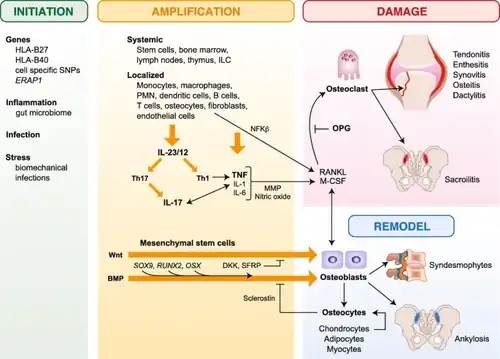

Mechanism

The arthritogenic-peptide theory is the classic pathophysiological paradigm for spondyloarthritis. It argues that HLA-B27 displays self-peptides that resemble pathogen-derived peptides to CD8-restricted T cells. Two other theories have been proposed to explain HLA-B27's function. They suggest that HLA-B27's genesis may be autoinflammatory rather than autoimmune, as it plays a part in initiating innate immune responses instead of its traditional function of presenting antigens.[2]

According to the first hypothesis, HLA-B27 heavy chains devoid of β2 microglobulin can form disulphide-linked homodimers that are produced at the cell surface and can be recognized directly by KIR3DL2 killer immunoglobulin-like receptors, regardless of the associated peptide.[19][20]

According to the second hypothesis, the B pocket's Cys 67 residue causes HLA-B27 heavy-chain misfolding in the endoplasmic reticulum before assembling into complexes with peptide and β2 microglobulin.[21][22] As a result, the unfolded protein response (UPR) modifies the immune cells' cytokine output and reactivity to various innate immunological stimuli.[23][24][25]